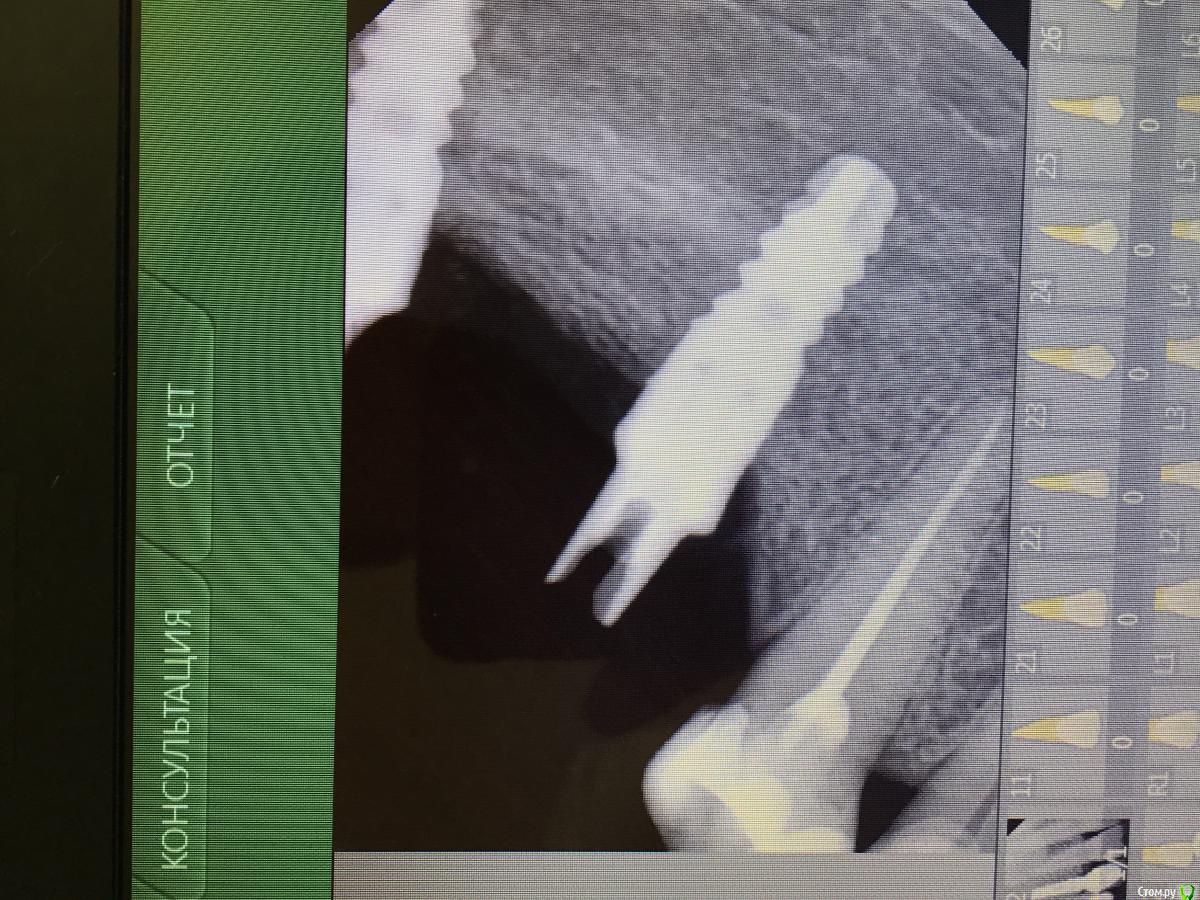

Oleg Mikhaylyuk Опубликовано 15 марта, 2017 Поделиться Опубликовано 15 марта, 2017 (изменено) Коллеги, как открутить такой абатмент, я так понимаю винт повержден?? Изменено 15 марта, 2017 пользователем Oleg Mikhaylyuk Ссылка на комментарий